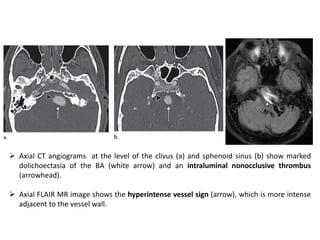

 Axial CT angiograms at the level of the clivus (a) and sphenoid sinus (b) show marked

dolichoectasia of the BA (white arrow) and an intraluminal nonocclusive thrombus

(arrowhead).

 Axial FLAIR MR image shows the hyperintense vessel sign (arrow), which is more intense

adjacent to the vessel wall.